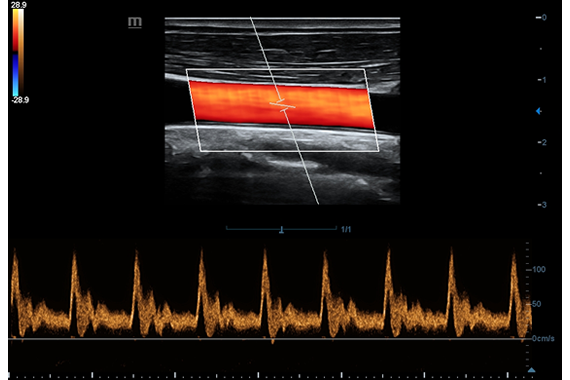

• HR Flow - режим отображения кровотока с высоким временным и пространственным разрешением для точной и однородной визуализации сосудов, в том числе самых мелких.

Цветовой допплер:

Да

Импульсно-волновой допплер:

• Vascular package - предустановленные параметры, аннотации, маркеры, программы измерений для ангиологии, включая транскраниальные исследования